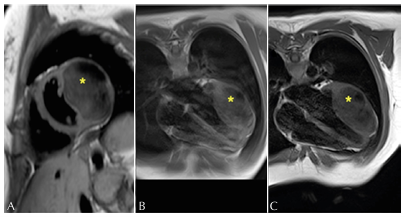

Figure 2: Short axis (A) and four-chamber (B-C), presenting intramyocardial mass (*) isointense in T1. 2016 (A), 2018 (B), and 2020 (C).